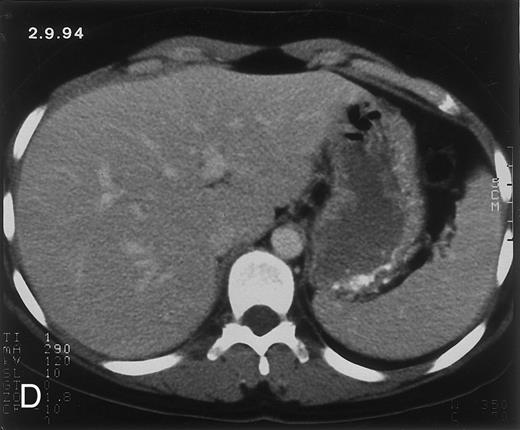

(C) On June 6, 31 days after normalization of neutrophils, CT again shows multiple lesions in the liver (arrowheads) with a different presentation: the small lesions show strong peripheral enhancement. (D) On September 2, 129 days after neutrophil recovery, all hepatic lesions have completely resolved.

Radiologic evolution in patient B. (A) Postcontrast abdominal CT scan on February 10, 1994 shows multiple small hypodense areas in all segments of the liver suggestive of hepatic candidiasis. Twenty-four days previously, the patient had recovered from severe neutropenia after the second cycle of chemotherapy for ALL. (B) On May 4, 16 days after the neutrophil count had dropped below 500/μL in the third chemotherapy cycle, there is clear improvement of the radiologic findings, with only a few hypodense areas in the liver.

Evolution of fungal lesions on CT scans during and after neutropenia is summarized in Table 2. Figure 1 (patient A) and Fig 2 (patient B) serve to illustrate Table 2.

In three patients, multiple round lesions were seen on postcontrast CT scans of the abdomen in the liver and the spleen, while in two cases, lesions could only be seen in the liver (Table 2). Following the diagnosis of disseminated candidiasis, these lesions decreased in size and visibility during subsequent neutropenia in three patients (compare Fig 2A and B) and disappeared completely in two patients (compare Fig 1A and B). The numbers of days of severe neutropenia (neutrophils <500/μL) at the time the CT scan was performed are listed in Table 2. After recovery from neutropenia and despite continued antifungal therapy, the size and visibility of the lesions increased again (Fig 1C). Similarly, the number of days since recovery from severe neutropenia (neutrophils >500/μL) are listed in Table 2. In two of three patients treated with another cycle of myeloablative chemotherapy, this waxing and waning pattern of radiologic lesions could be seen again (Fig 1D and E). In all patients, lesions eventually disappeared (Figs 1F and 2D) after prolonged antifungal therapy.